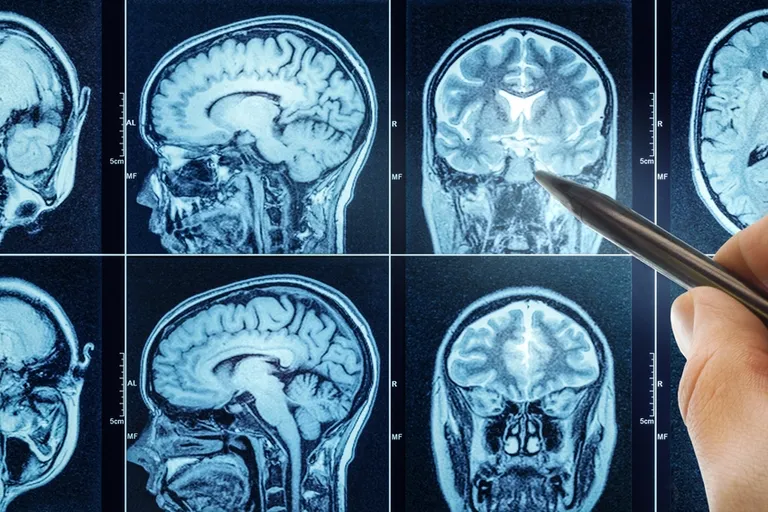

“Važno je pri sumnji na multiplu sklerozu uputiti pacijenta neurologu koji će na temelju anamneze, neurološkog pregleda te dijagnostičkih pretraga koje uključuju magnetsku rezonancu mozga i vratne kralježnice, lumbalnu punkciju te vidne i slušne potencijale, uz dodatne pretrage) postaviti ili isključiti primarnu demijelinizaciju po tipu multiple skleroze. Magnetska rezonancija je najbolji test za otkrivanje multiple skleroze. Obično otkriva područja demijelinizacije u mozgu i leđnoj moždini. Dodatni testovi uključuju lumbalnu punkciju i evocirane potencijale”, dodala je.